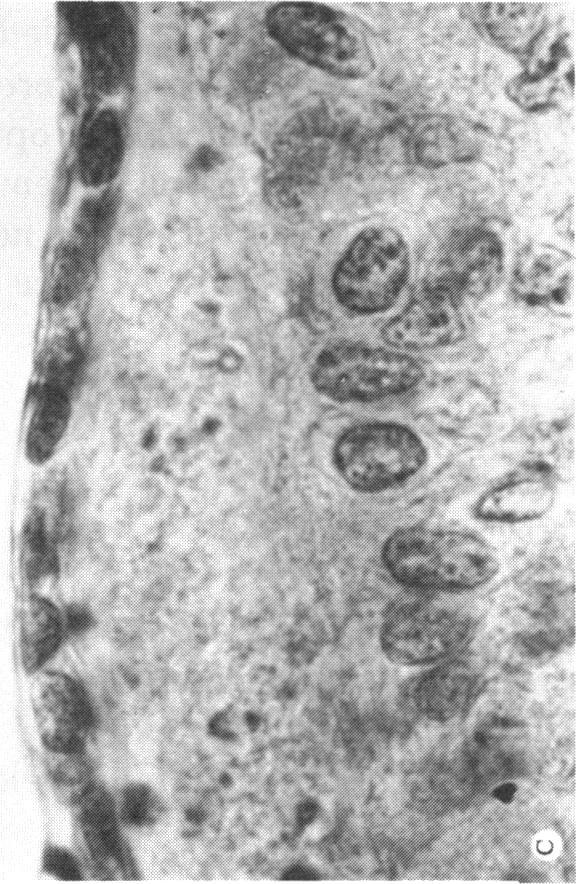

At the present time, essentially all known facts concerning cyclopia are consistent with some chromosomal disease, including clinical features of the pregnancy (fetal wastage, prematurity, intrauterine growth retardation, maternal age factor, complications of pregnancy), the generalized developmental abnormalities, specific ocular dysgenesis, by the high incidence of chromosomal abnormality already demonstrated, and the possibility of error in those cases of cyclopia with normal chromosomes. Even if chromosomal aberrations represent only one group of several different etiologic factors leading to cyclopia, at the present time chromosomal errors would seem to be the most common cause of cyclopia now recognized. Further studies will establish or disprove a chromosomal error in those instances which are now considered to be the result of an environmental factor alone or those with apparent familial patterns of inheritance. This apparent diverse origin of cyclopia can be clarified if future cyclopic specimens are carefully investigated. The evaluation should include a careful gross and microscopic examination of all organs, including the eye, and chromosome banding studies of all organs, including the eye, and chromosome banding studies of at least two cyclopic tissues. Then the presence or absence of multiple causative factors can be better evaluated.

目前,基本上所有关于独眼畸形的已知事实都与某些染色体疾病相符,包括妊娠的临床特征(胎儿死亡、早产、宫内生长迟缓、母亲年龄因素、妊娠并发症)、全身性发育异常、特定的眼发育不全,以及已证实的染色体异常的高发生率,还有那些染色体正常的独眼畸形病例存在错误的可能性。即使染色体畸变只是导致独眼畸形的几种不同病因中的一组,目前染色体错误似乎是现在所认识到的独眼畸形最常见的原因。进一步的研究将证实或否定那些目前被认为仅由环境因素导致或具有明显家族遗传模式的病例中的染色体错误。如果对未来的独眼畸形标本进行仔细研究,这种明显多样的独眼畸形起源可能会得到阐明。评估应包括对所有器官,包括眼睛,进行仔细的大体和显微镜检查,以及对所有器官,包括眼睛,进行染色体显带研究,并且至少对两个独眼畸形组织进行染色体显带研究。这样就能更好地评估多种致病因素的存在与否。